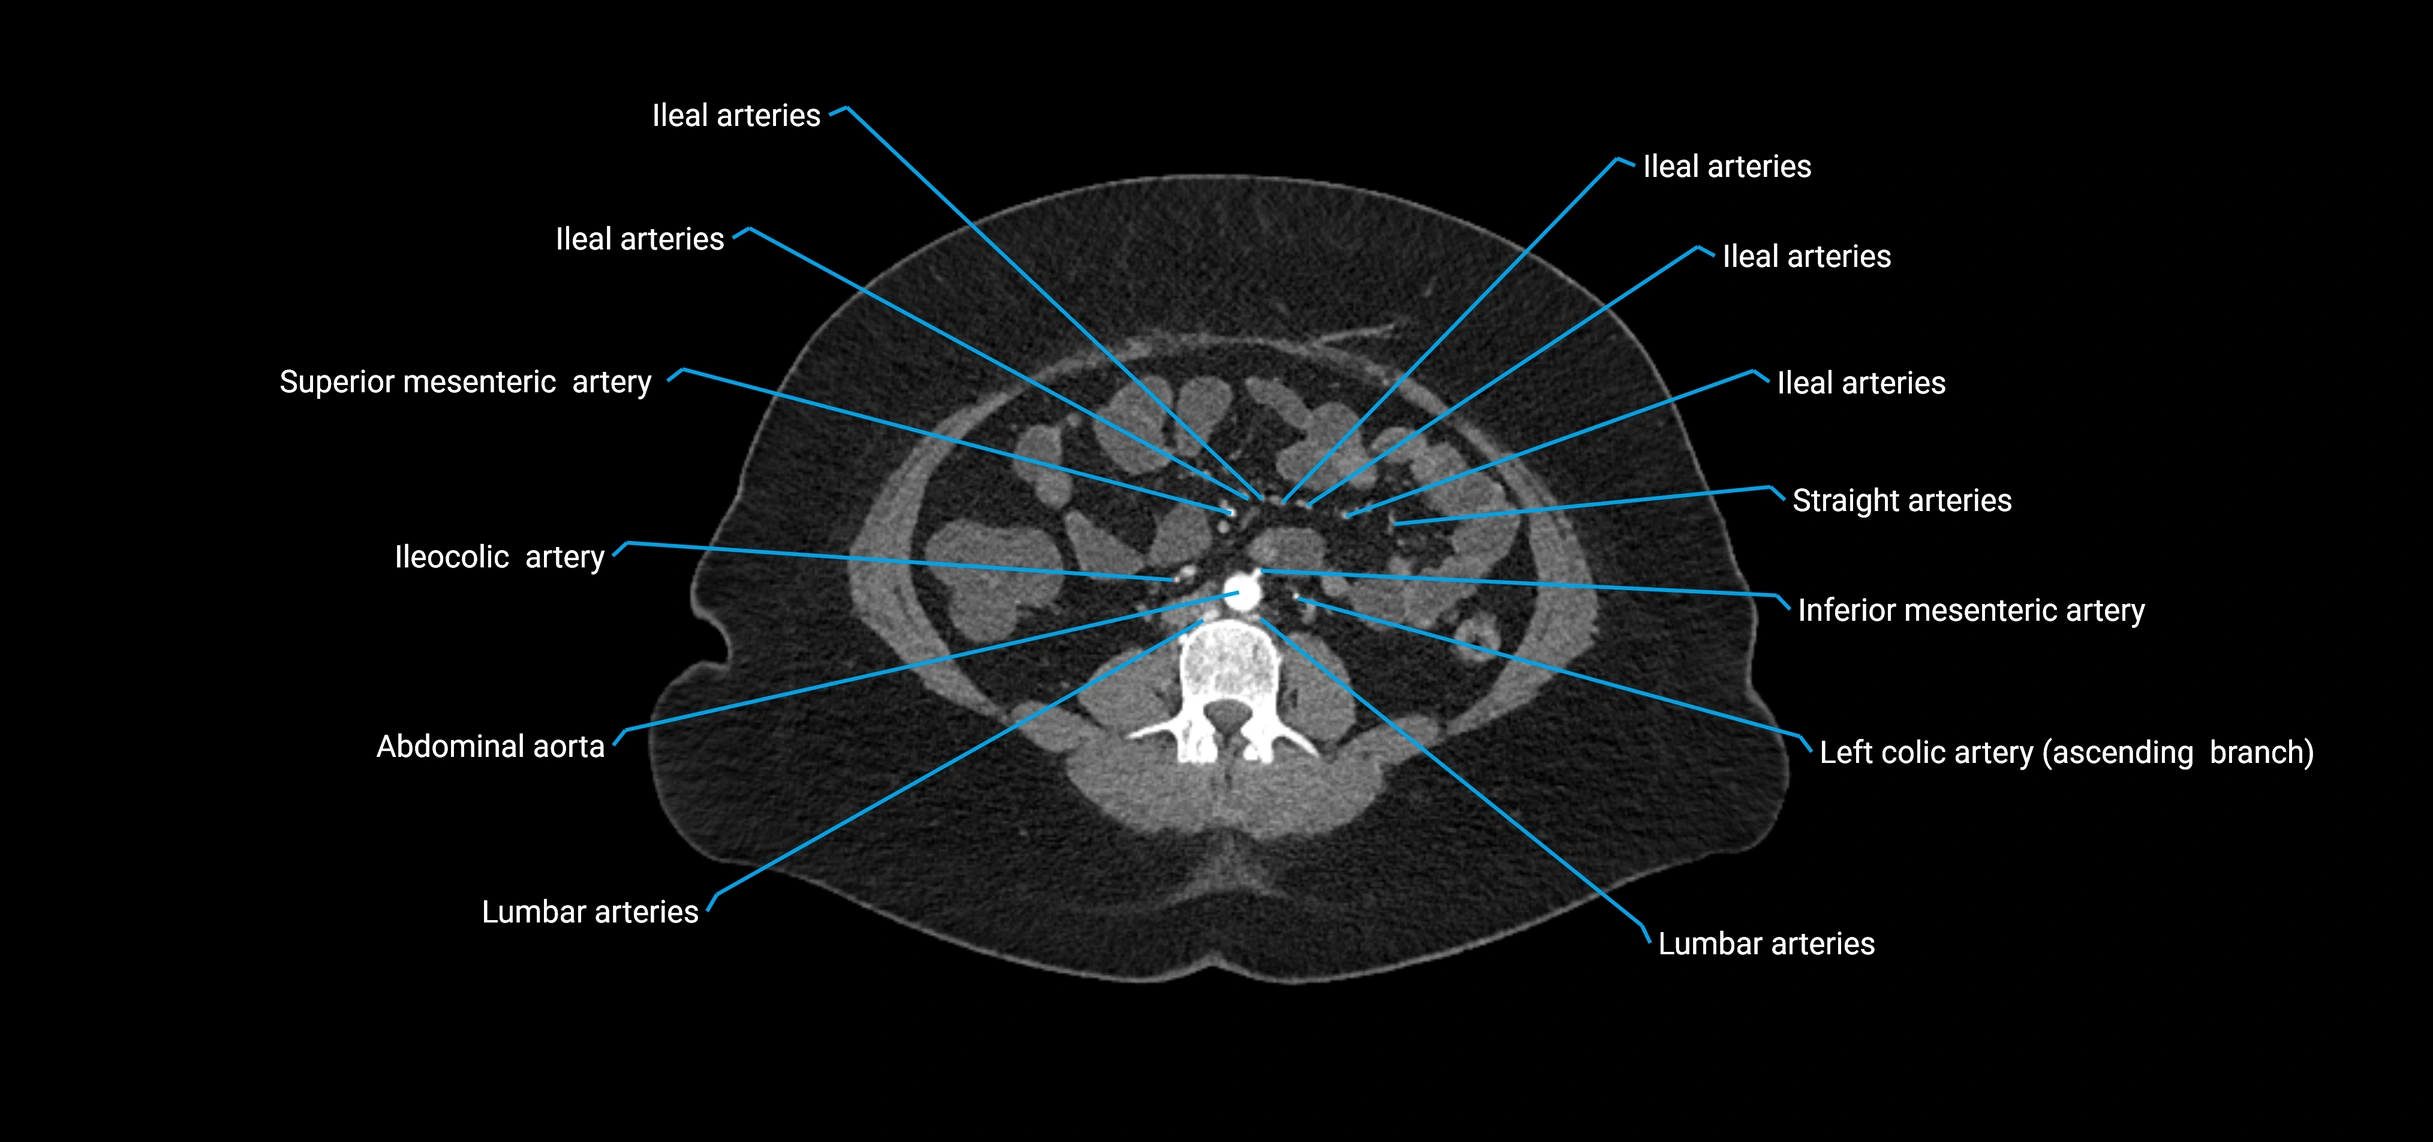

Contrast-enhanced CT (CTA):

• Gold standard for abdominal aortic imaging

• Provides excellent detail of lumen, wall, aneurysm, thrombus, and branch vessels

• Multiplanar and 3D reconstructions help in aneurysm measurement, stent graft planning, and dissection evaluation